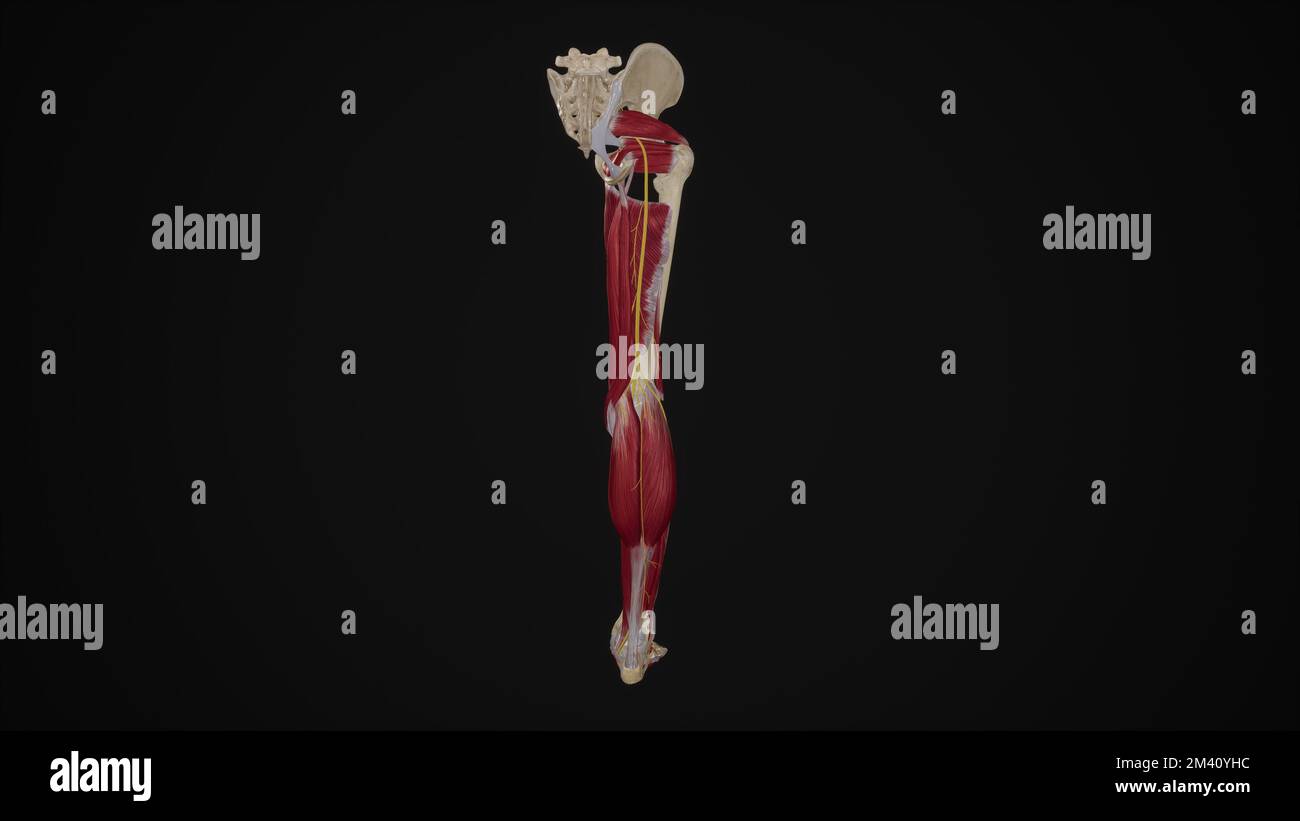

Nerf sciatique sur fond noir.3D rendu Banque D'Imageshttps://www.alamyimages.fr/image-license-details/?v=1https://www.alamyimages.fr/nerf-sciatique-sur-fond-noir-3d-rendu-image501580952.html

Nerf sciatique sur fond noir.3D rendu Banque D'Imageshttps://www.alamyimages.fr/image-license-details/?v=1https://www.alamyimages.fr/nerf-sciatique-sur-fond-noir-3d-rendu-image501580952.htmlRF2M40YHC–Nerf sciatique sur fond noir.3D rendu